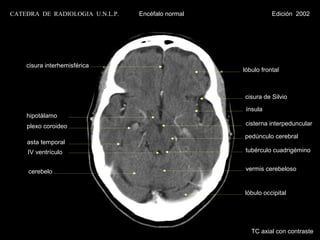

CATEDRA DE RADIOLOGIA U.N.L.P.   Encéfalo normal              Edición 2002

cisura interhemisférica

lóbulo frontal

cisura de Silvio

ínsula

hipotálamo

plexo coroideo                                 cisterna interpeduncular

pedúnculo cerebral

asta temporal

IV ventrículo                                  tubérculo cuadrigémino

cerebelo                                       vermis cerebeloso

lóbulo occipital

TC axial con contraste